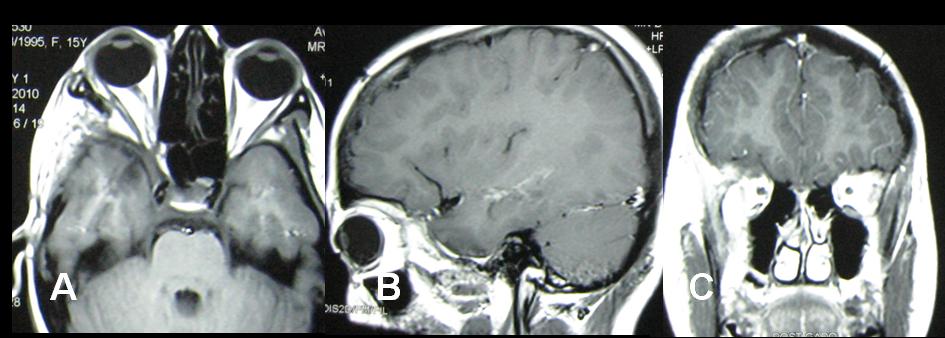

Preoperative malignant looking retrobulbar, infratemporal and middle cranial fossa tuberculoma in a young child - a case report

Tuberculosis involving skull base and brain is relatively common in developing countries. Preoperative neuro-radiological features of such lesions mimic neoplastic lesions of brain & skull base and postoperative histopathological study brings the ultimate diagnosis. Here we present a case of large tubercular lesion involving retrobulbar, infratemporal and middle cranial fossa that preoperatively thought to be a malignant lesion in a young child and was managed surgically with anti-tubercular drugs having a happy termination. Even radiologically malignant looking mass lesion in brain and skull base can be proved as tuberculosis that can bring happiness to the patient and also to the treating neurosurgeons.